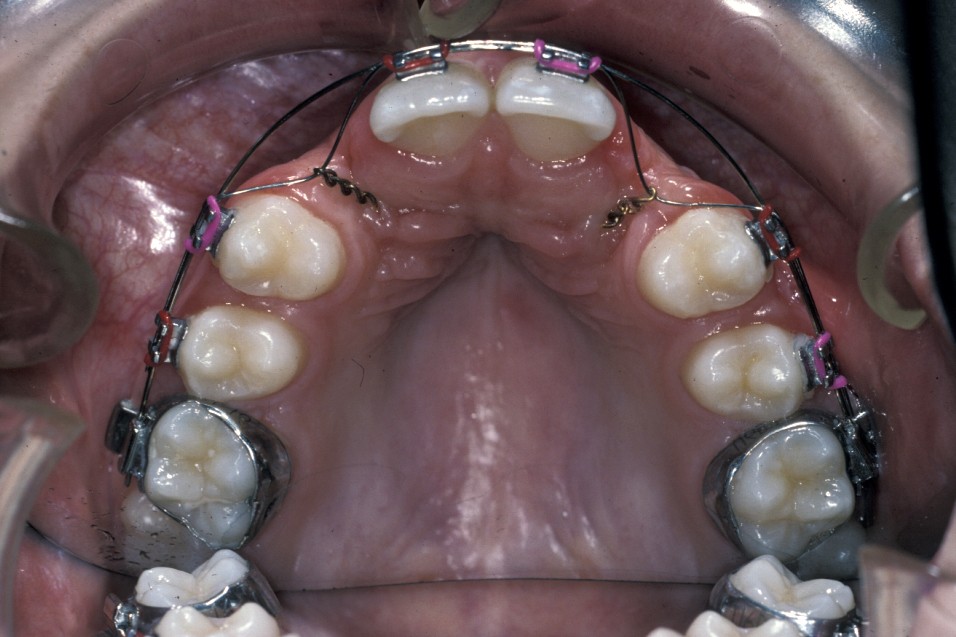

For satisfactory results to be achieved by surgical exposure and alignment of ectopic canines, complex fixed-appliances treatment for sometimes in excess of two years is required. Such appliances may include the need for dual-arch fixed appliances to allow for the use of interarch elastics and to allow arch co-ordination.

Before surgery is undertaken a decision has to be made between open or closed eruption. The aim of any exposure is to uncover enough of the crown either to place an attachment or prevent recovering of the crown during the healing phase. The most important principle of surgery is to ensure the tooth will erupt through keratinized mucosa. If this does not happen, which can occur with buccally placed canines, then the post-treatment periodontal condition will be compromised. This can obviously affect gingival aesthetics and health.

Closed eruption uses an attachment secured to the tooth to apply orthodontic traction and is useful in the treatment of markedly ectopic teeth where it would be difficult to undertake an adequate open exposure. It is often used when the canine is palatally positioned. It can be used for the treatment of buccal canines but the results can be disappointing if the attachment herniates through the thin buccal gingivae. To avoid this, the attachment should be placed either on the tip of the tooth or palatally. This is sometimes not possible because the crown position increases the risk of either excessive bone removal or iatrogenic damage to adjacent structures. It is, however, useful in the treatment of buccal canines if the crown overlies an adjacent tooth and it would be difficult to undertake an apically repositioned flap.

Surgery involves the same access as for the removal of the tooth, except that great care must be taken not to damage the cementum of the root surface as this can lead to ankylosis of the tooth and subsequent failure of eruption. An adequate amount of the crown should be exposed to allow attachment of the bracket and chain. Prior to bonding the bracket to the tooth, the area should be as uncontaminated as possible. Bleeding should be arrested as much as practicable with the use of local application of vasoconstrictors (as is added to some local anaesthetics) or the use of diathermy. Once the area is prepared, the tooth surface should be washed with saline or water and then prepared for bonding either with acid etch or with self-etch priming agents. The latter offer the advantage that they do not need to be rinsed off, need less time to prepare the tooth and are to some extent hydrophilic.

Once the tooth surface has been prepared the bracket can be secured either with chemical- or light-cured composite. The bracket should be tested to ensure that it is securely in place prior to wound closure. The chain or ligature can either exit through the wound margin on the alveolar ridge or through a stab incision elsewhere if it is felt that this would give a better vector of traction to align the tooth. With teeth that are significantly ectopic or are close to the roots of adjacent teeth, it is sometimes useful for the orthodontist to be present at the time of surgery. This allows an assessment of the relationship of the canine to adjacent structures and to plan the vector of traction that will be most appropriate.

- Palatally placed canines - open eruption can also be used in the treatment of palatally ectopic canines, especially when they are relatively superficial. As the palatal mucosa is all keratinized, the problem of ensuring that the tooth erupts through here is to ensure adequate crown is exposed to ensure that there is no chance of the crown becoming recovered during the healing phase. If necessary, a bracket can be attached at the time of surgery in the same manner as for closed eruption. Care must be taken to ensure that the cementum is not damaged during surgery and that keratinized mucosa is left overlying the cementum - enamel junction. Interestingly even if large areas of bone are left denuded after surgery healing is usually excellent and uneventful. Packs can be placed over the exposed tooth to aid haemostasis, comfort and to prevent the tooth becoming covered again. This has historically involved the placing of ribbon gauze soaked in varnish and secured in place with mattress type sutures. Periodontal dressing can also be used. The pack should be removed after 7 to 14 days, from when on vigorous oral hygiene measures are vital to encourage healing, prevent gingival overgrowth and encourage eruption (Figure 19 and Figure 20).